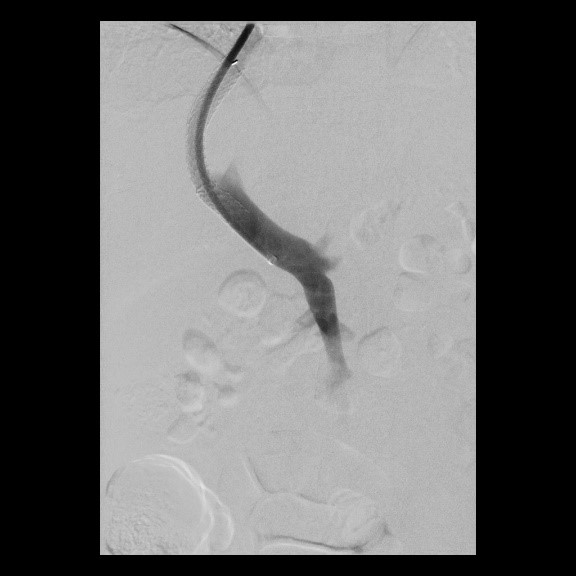

« Zurück Erfolgreiche Implantation eines transjugulären intrahepatischen portosystemischen Shunts (TIPSS) bei Leberzirrhose und refraktärem Aszites. Transhepatische Punktion der Pfortader unter sonographischer Kontrolle (Bild 3 von 4) Vorwärts »

« Zurück Erfolgreiche Implantation eines transjugulären intrahepatischen portosystemischen Shunts (TIPSS) bei Leberzirrhose und refraktärem Aszites. Implantation eines Stentgrafts (Bild 4 von 4)